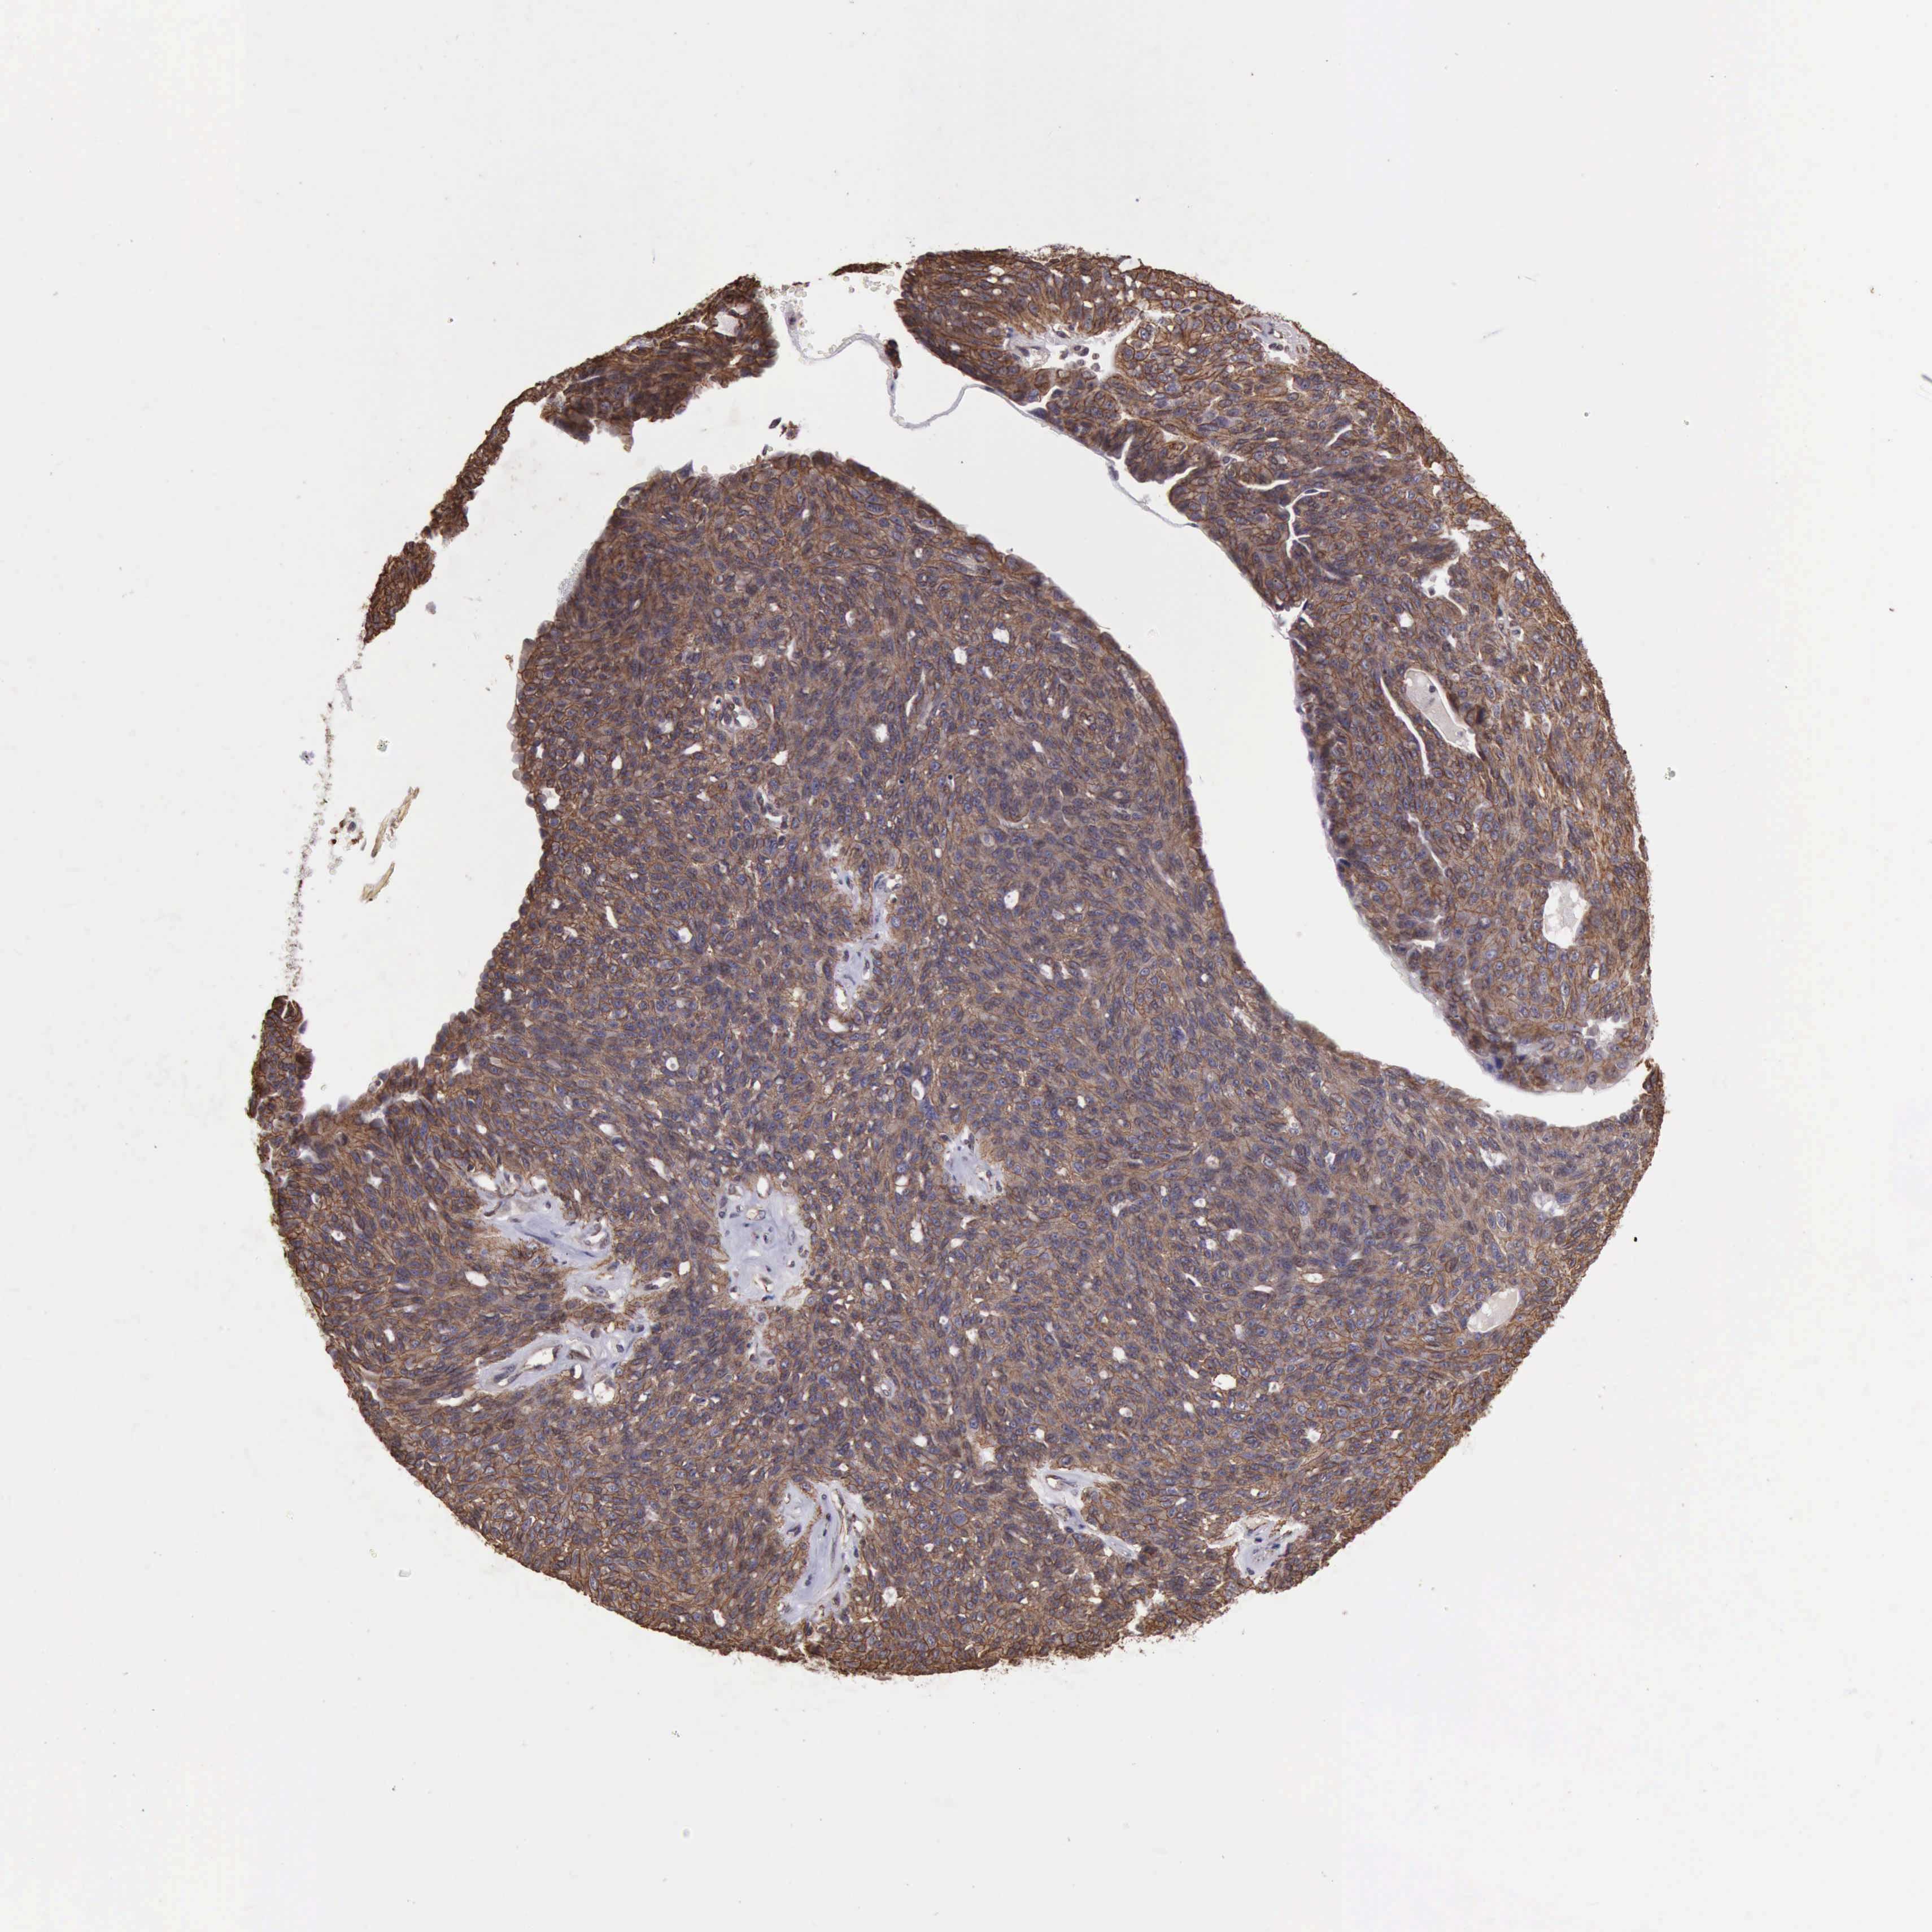

OVARIAN CANCER - Protein expressioni

A mouse-over function shows sample information and annotation data. Click on an image to view it in a full screen mode. Samples can be filtered based on level of antibody staining by selecting one or several of the following categories: high, medium, low and not detected. The assay and annotation is described here.

Note that samples used for immunohistochemistry by the Human Protein Atlas do not correspond to samples in the TCGA dataset.

Antibody stainingi

Antibody staining in the annotated cell types in the current human tissue is reported as not detected, low, medium, or high, based on conventional immunohistochemistry profiling in selected tissues. This score is based on the combination of the staining intensity and fraction of stained cells.

Each image is clickable and will lead to virtual microscopy that enables deeper exploration of all samples and also displays staining intensity scores, fraction scores and subcellular localization as well as patient and tissue information for each sample.

Antibody HPA029159

Antibody HPA029160

Antibody CAB000108

Antibody CAB001950

Staining

High

Medium

Low

Not detected

Cystadenocarcinoma, serous, NOS